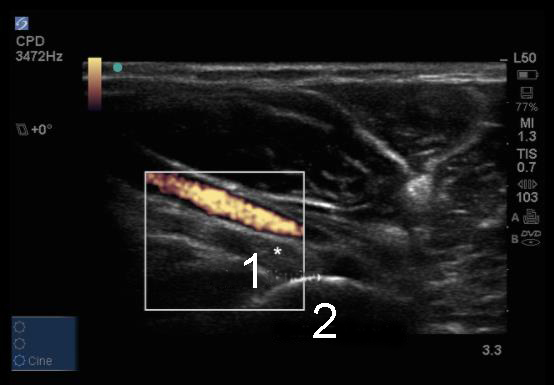

肘のCPD上腕動脈を伴う遠位上腕二頭筋の画像

上腕二頭筋腱

橈骨粗面